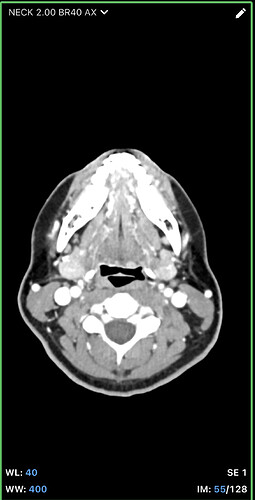

I think the best CT imaging view to look at whether your hyoid is digging into anything is by going into the axial view of your imaging. In the axial view look for the horseshoe shaped hyoid bone. I’ve attached what to look for. Take a couple screen shots and upload them and I can help interpret the imaging.

@leo this is the closest one. Can you go back to your axial view and go to the very last slice that you can see the tips? I think you might be one or two frames off. I attached my imaging to help. Our hyoids might be at slightly different angles so it might not be a perfect comparison, but I think you can go up a slice or two to see the tips better. Basically follow the bone until it disappears then go back one frame to capture it.

Hi, I’m so sorry for the delay in replying to you, we had some family stuff come up and this got pushed to the back burner for awhile. I’ve gone back a few frames, am I getting closer? I can also send you the whole CT if that would make things easier. I’m sorry, I’m not good with technology. I appreciate you taking the time to respond! Since we last spoke, I’ve developed a lot of neurological symptoms and weird physical ones like dizziness, headaches, brain fog, weird throbbing in my neck and head, can this all be tied in with hyoid bone problems? Thank you so much for your time!